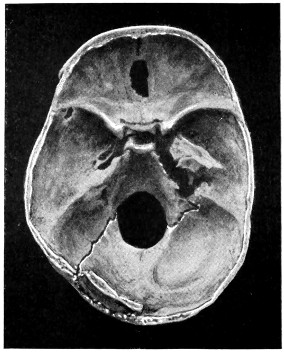

| 50 A and B. The inner aspect of the skull and the same seen on transillumination | 137 |

| 51. To illustrate compression of the brain as produced by an extra-dural hæmorrhage from the middle meningeal artery[x] | 141 |

| 52 A and B. The operative treatment of middle meningeal hæmorrhage | 144, 145 |

| 53. A basic fracture with laceration of both carotid arteries | 148 |

| 54. A basic fracture with laceration of the cavernous sinus | 149 |

| 55. A basic fracture with laceration of both lateral sinuses | 151 |